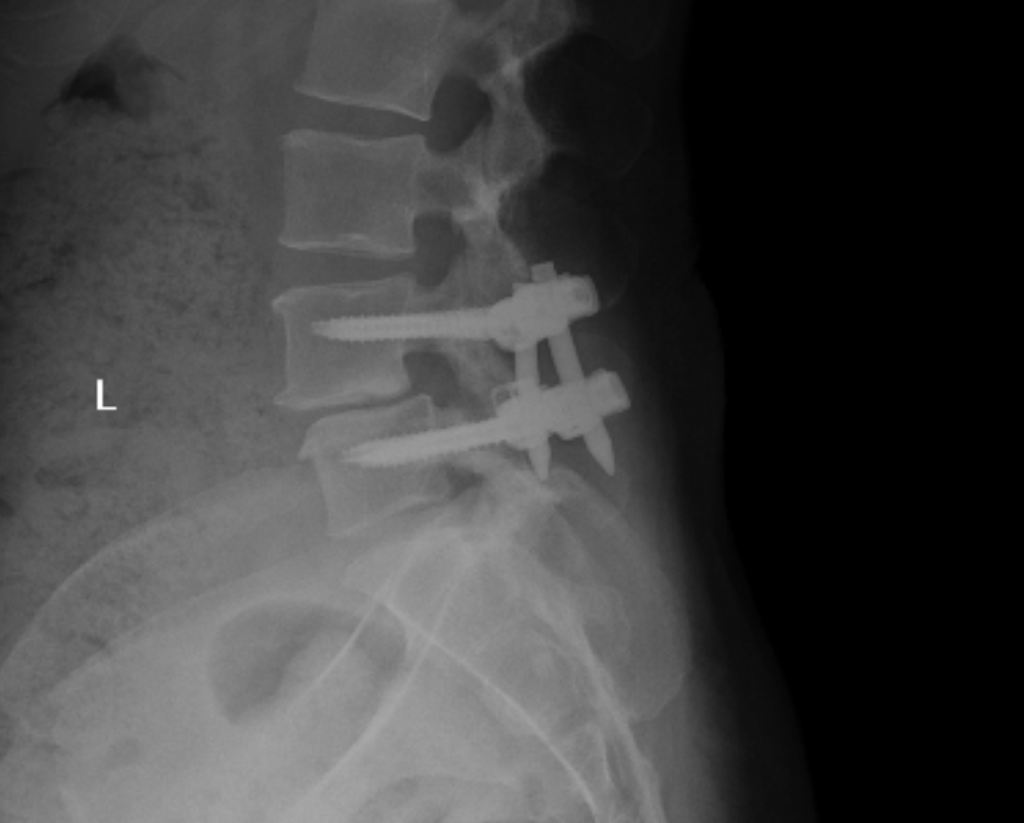

I’ve always been active. I’ve done everything - boxing, Pilates, barre, and in my mid-40s after Covid I started to run and ran two half marathons in 2022 and 2023. I first started to experience pain in my hip and down my right leg during my first pregnancy. The leg pain subsided but the hip pain never did. When I took up running, that’s when things went downhill. First the plantar fasciitis, then the constant leg pain like I had pulled a hamstring. Dr. Baxi at first used cortisone on both my foot and back. Then we did shockwave therapy on my foot which helped tremendously. But after a second epidural on my back didn’t work I knew it was time for surgery. Dr. Dowdell was great. It was tough at first and he assured me after six months I could get back to my former life. Now I’m back to boxing and I’m hoping to start training for and run in the NYC marathon this Fall.

James E. Dowdell III, MD

Spine Surgeon